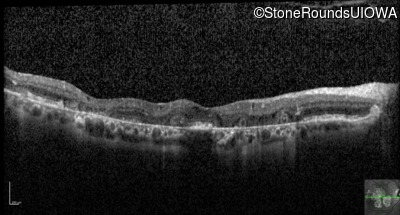

Optical Coherence Tomography - Left - 20/25 -2

Exemplar / OCT Stack

OCT Stack